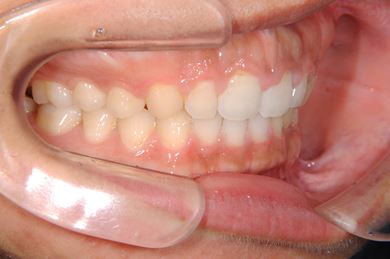

| 性別/年齢 | 女性 / 22歳 | ||||||||||||||||||||||||||||||||

| 主訴 | 前歯の隙間 | ||||||||||||||||||||||||||||||||

| 治療方針 | 舌が前に出てしまったり、左下の糸切り歯が一本足りないことで、上下の歯に隙間がある状態です。口元はきれいなので、非抜歯にて治療を開始しました。顎のずれがあるので、上下にゴムを使用しながら、また舌の練習をしながら治療しました。左下の欠損部にはデンタルインプラントで補綴し咬合させました。保定装置は隙間が出ないように上下とも裏から針金を装着しています。非抜歯治療で治療期間が1年半と予想していましたが、舌の癖があまり改善されなく、2年と治療期間が延びてしまいました。今後も舌が出ないように気を付けていただきます。保定装置の使用も初診時に説明し、診断時の治療計画にも記載していましたが、きちんと理解されていなかったようで、除去後保定装置の使用にショックを受けさせてしまいました。今後また改善していきたいと思います。頑張って咬合の維持をしていきましょう。 | ||||||||||||||||||||||||||||||||

| 治療内容 | 唇側矯正(ホワイト・非抜歯)、インプラント1本、メタルボンドセラミック1本 | ||||||||||||||||||||||||||||||||